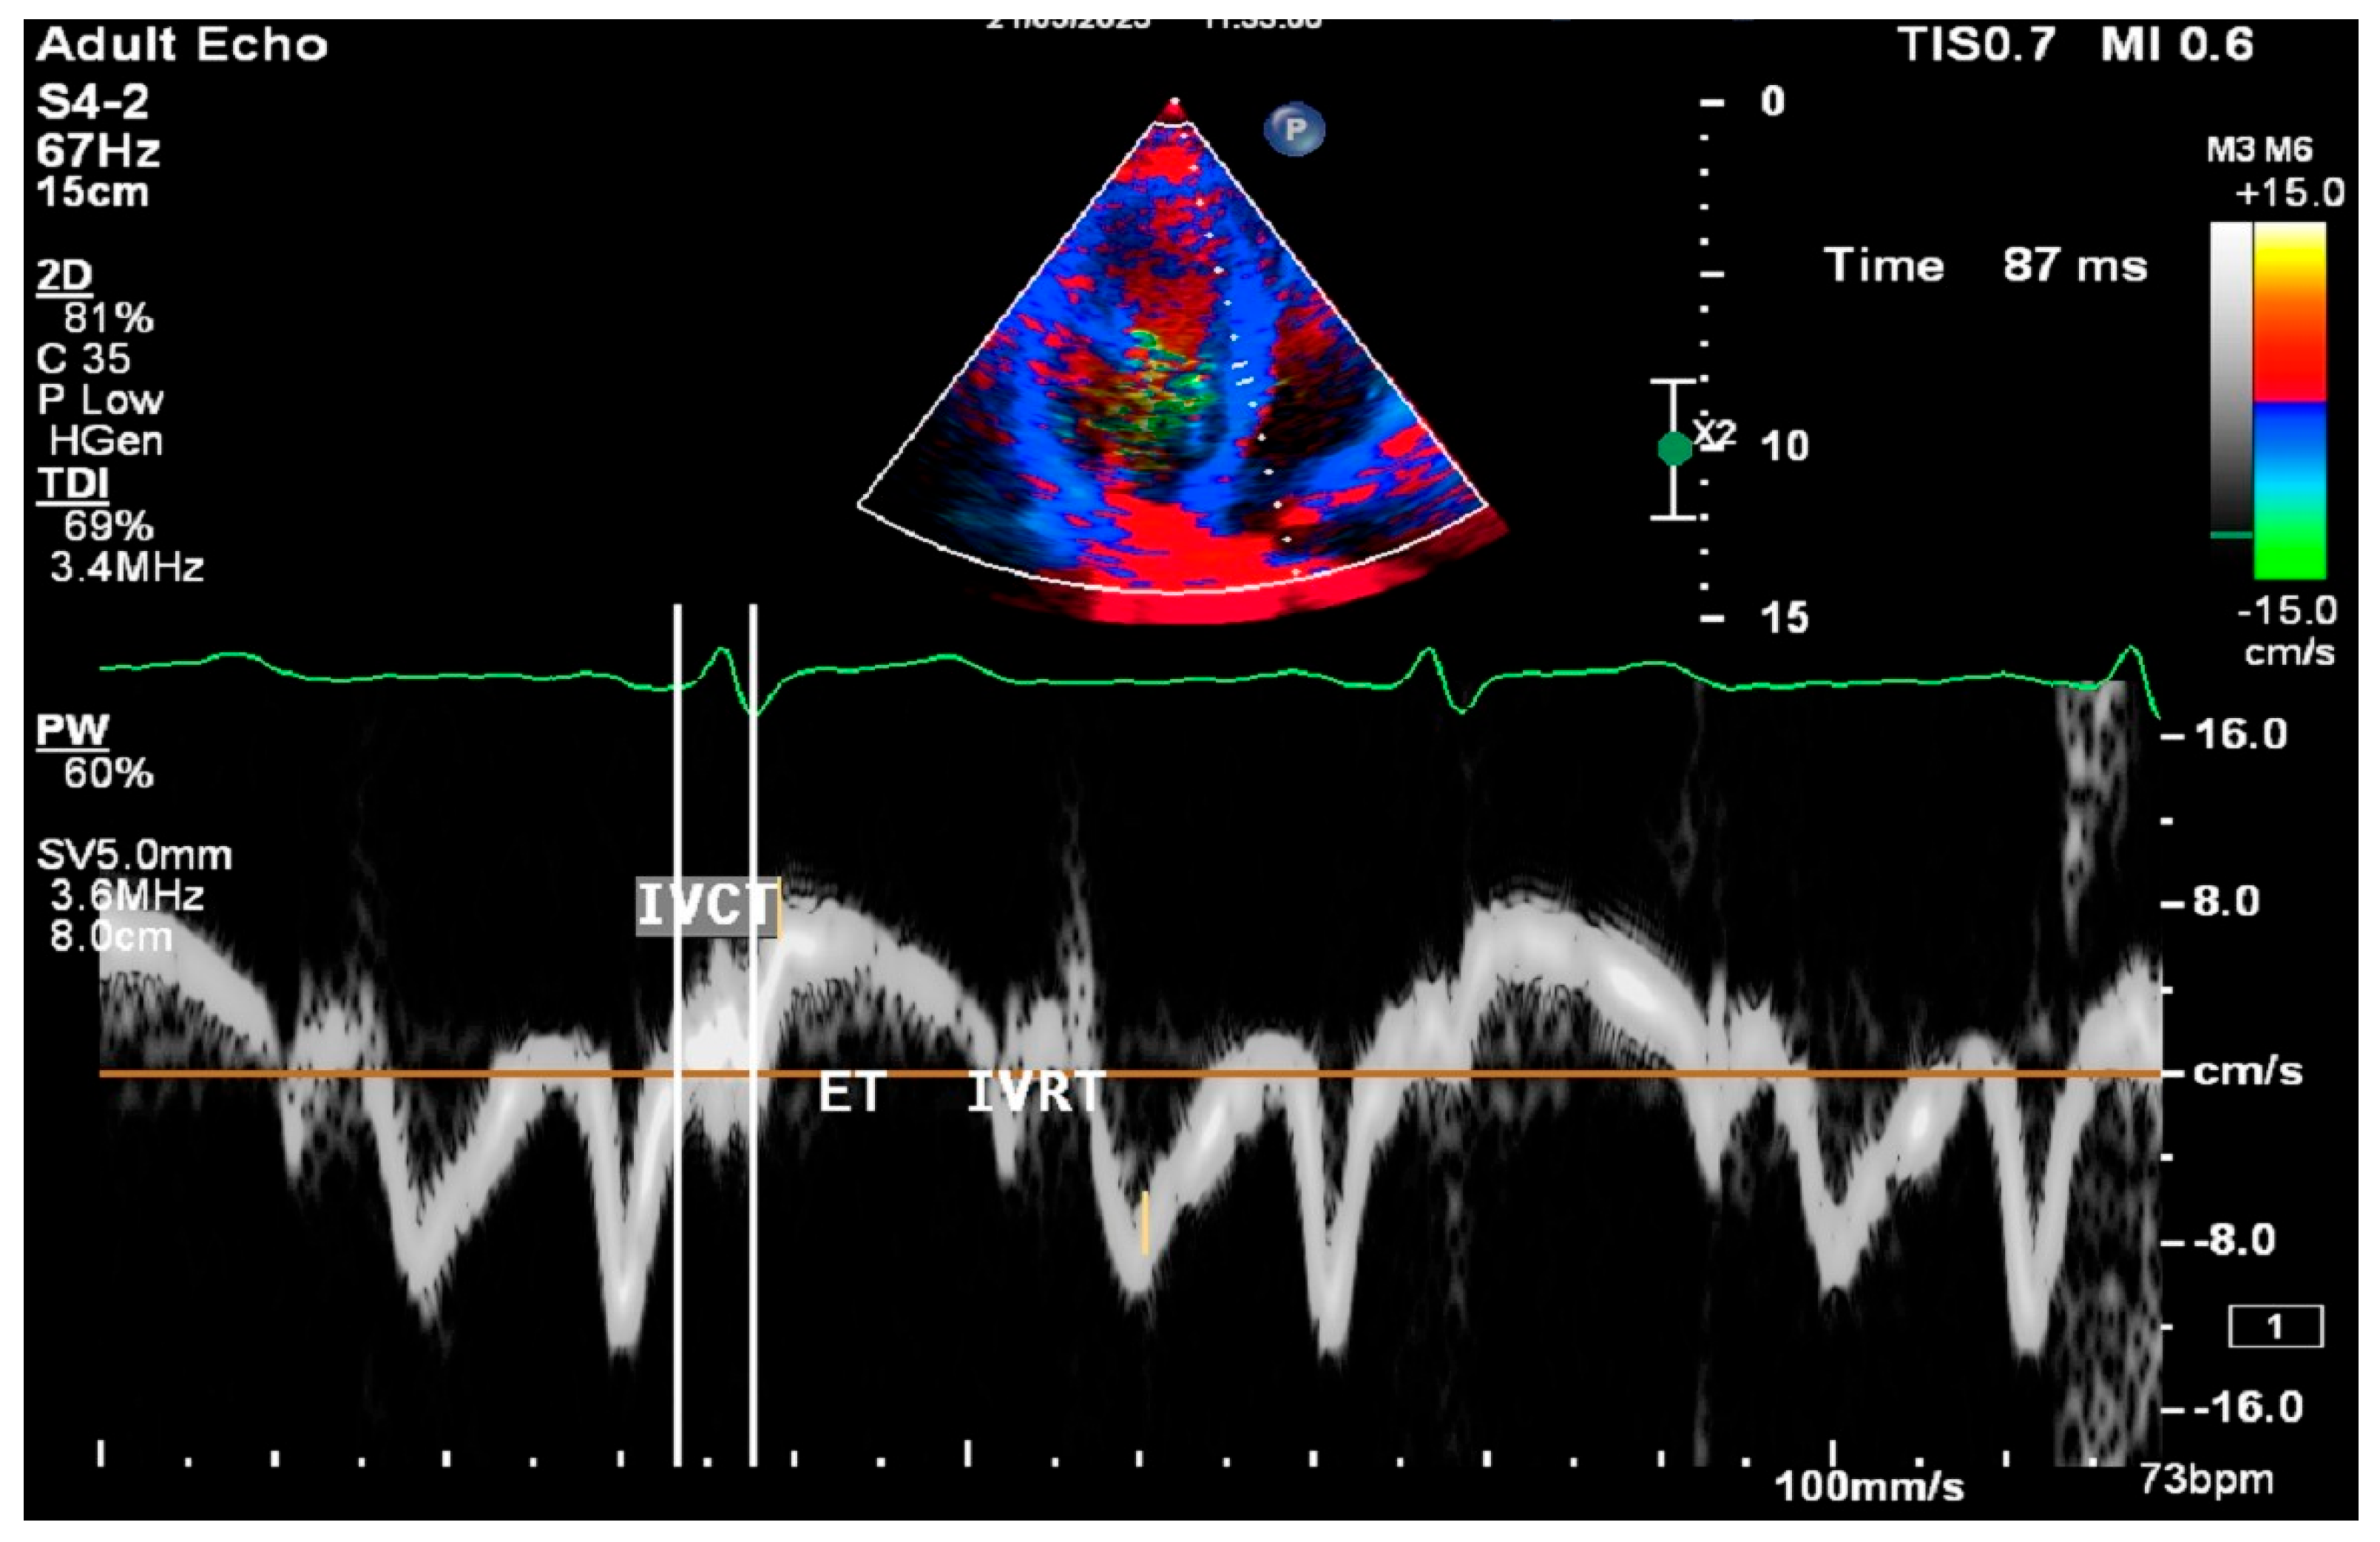

2.8. Cardiac Ultrasound Examinations

All procedures were performed using Philips Epiq 7 ultrasound systems (Philips Ultrasound; Bothel, WA, USA) and a 2.5 MHz FPA probe. Conventional M-mode, B-mode, and Doppler parameters were measured according to the American Society of Echocardiography guidelines [8]. Left ventricular end-diastolic diameter (LVDd), left ventricular end-systolic diameter (LVDs), posterior wall (PW), and interventricular septum (IVS) thicknesses were measured. Left ventricular ejection fraction (LVEF) was measured from the apical four-chamber view using the Modified Simpson method. Mitral E, A waves, and E wave deceleration time were obtained by PW Doppler placed at the tip of the mitral leaflets in the apical four-chamber window. E/A ratios were calculated for each patient. Measurements were made by placing tissue Doppler on the septal and lateral edges of the mitral valve in the apical four-chamber window. Early diastolic peak (Em), late diastolic peak (Am), and peak systolic flow (Sm) velocities were measured. Isovolumetric relaxation time (IVRT), isovolumetric contraction time (IVCT), and ejection time (ET) were also found (Figure 2).

Figure 2.

Test image in conventional M-mode, B-mode, and Doppler parameters.

The myocardial performance index (MPI) was calculated using the data obtained from Doppler echocardiography and the following formula [9]. Patients with an MPI of 0.5 and above were defined as having subclinical left ventricular dysfunction (SCLVD) [10]. The left ventricular outflow tract (LVOT) flow was assessed by pulse wave Doppler in the apical five-chamber window immediately adjacent to the aortic valve.